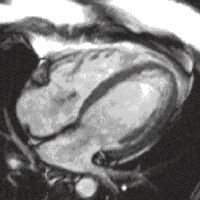

Images of the heart may be acquired in real-time with CMR, but the image quality is limited. Instead most sequences use ECG gating to acquire images at each stage of the cardiac cycle over several heart beats. This technique forms the basis of functional assessment by CMR. Blood typically appears bright in these sequences due to the contrast properties of blood and its rapid flow. The technique can discriminate very well between blood and myocardium. The current technique typically used for this is called balanced steady state free precession (bSSFP), implemented as TrueFISP, b-FFE or Fiesta, depending on scanner manufacturer.

A 4 chamber view of the heart using SSFP cine imaging. Compare the image orientation (4 chamber) with the short axis view of the movie above